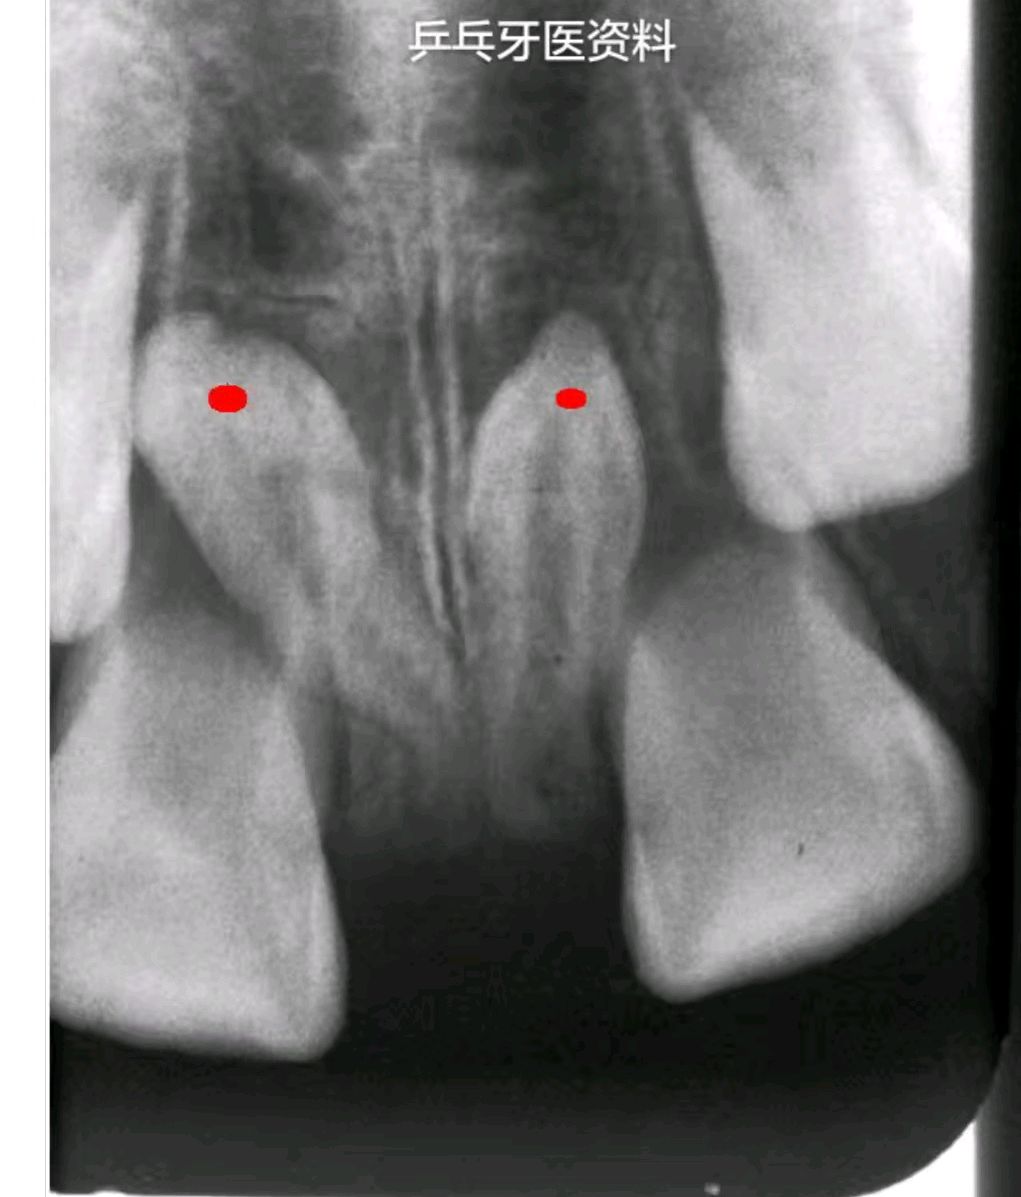

1.门牙间隙

多生牙导致门牙阻生